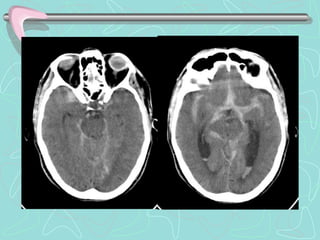

B.     HEMORRAGIA VENTRICULAR

 Colección de sangre en el interior de los

ventrículos cerebrales.

Primaria. Sangrado se localiza de forma exclusiva

en el sistema ventricular.

Secundaria . Originada en el espacio subaracnoideo

o en el parénquima y que se ha extendido al

sistema ventricular.